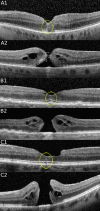

Purpose: To determine the prevalence of a central hyperreflective line in eyes with full-thickness macular holes (FTMH) and lamellar macular holes (LMH) and to elucidate the pathoanatomic importance of this optical coherence tomography (OCT) sign.

Methods: This retrospective analysis evaluated patients with FTMH and LMH at the Stein Eye Institute. Clinical data was collected and SD-OCT volume scans were analyzed for the presence of a central vertical hyperreflective line in 3 separate cohorts: patients with SD-OCT preceding FTMH development, patients with SD-OCT after pars plana vitrectomy (PPVT) treatment for FTMH, and patients with SD-OCT of LMH.

Results: In total, 93 eyes with FTMH and 88 eyes with LMH were identified. Of the 93 FTMH eyes, SD-OCT volume scans were available before development of the FTMH in 12 eyes. Of these, 6 (50%) displayed a vertical hyperreflective line preceding the development of the FTMH. Fifty-one eyes underwent PPVT with resolution of the FTMH, and 26 displayed a hyperreflective line after resolution (51%). Of the 88 eyes with LMH, 22 displayed a hyperreflective line (25%). All hyperreflective lines were noted at the central fovea.

Conclusions: SD-OCT illustrated the presence of a central vertical hyperreflective line preceding FTMH and after resolution of FTMH after PPVT in approximately one-half of cases, and concurrent with LMH in 25% of cases. This vertical hyperreflective line may represent an early SD-OCT marker for the development of FTMH, and may be a sign of central foveal dehiscence owing to disruption of the Muller cell cone.